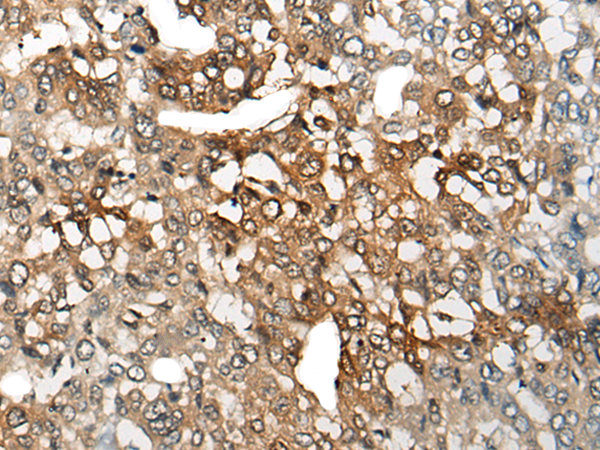

分类: 科研抗体货号: P09457别名: BL11; HB15应用: IHC反应种属: Human